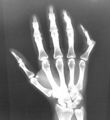

Dislocated left index finger

X-ray of right little finger dislocation

X-ray of left index finger dislocation